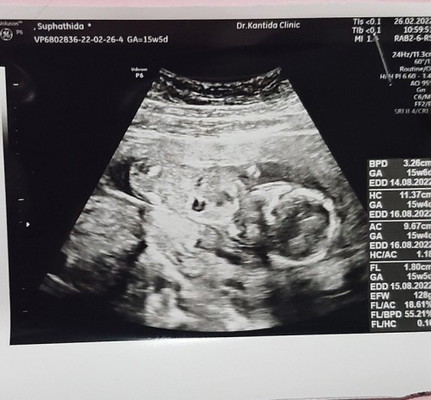

พอดีบ้านนี้ท้องได้16วีคแล้วค่ะ มีแต่คนทักว่าท้องไม่ออกเลย #ท้อง2แล้วค่ะ แต่พอไปซาวเมื่อวันเสาร์ที่ผ่านมาคุณหมอบอกน้องตัวโตดี นน.128กรัม ความยาวเท่าไรไม่ทราบค่ะ ถือว่ากำลังดีใช่ไหมคะแม่ๆ โดนทักบ่อยมากว่าสรุปมีเด็กอยู่ในท้องไหมเนี้ย🥺

14 วีค 128 กรัมเท่ากันเลยค่ะ ของเราท้องออกไวมากเลย 😂 อ้วนตั้งแต่ในท้องเลย 🤣